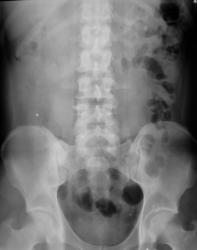

Иллюстрации 4, 5. В малом тазу справа на уровне последнего крестцового позвонка определяется тень характера конкремента, располагающаяся, вероятнее всего, в нижней трети правого мочеточника.

В малом тазу с обеих сторон тени флеболитов различных размеров.